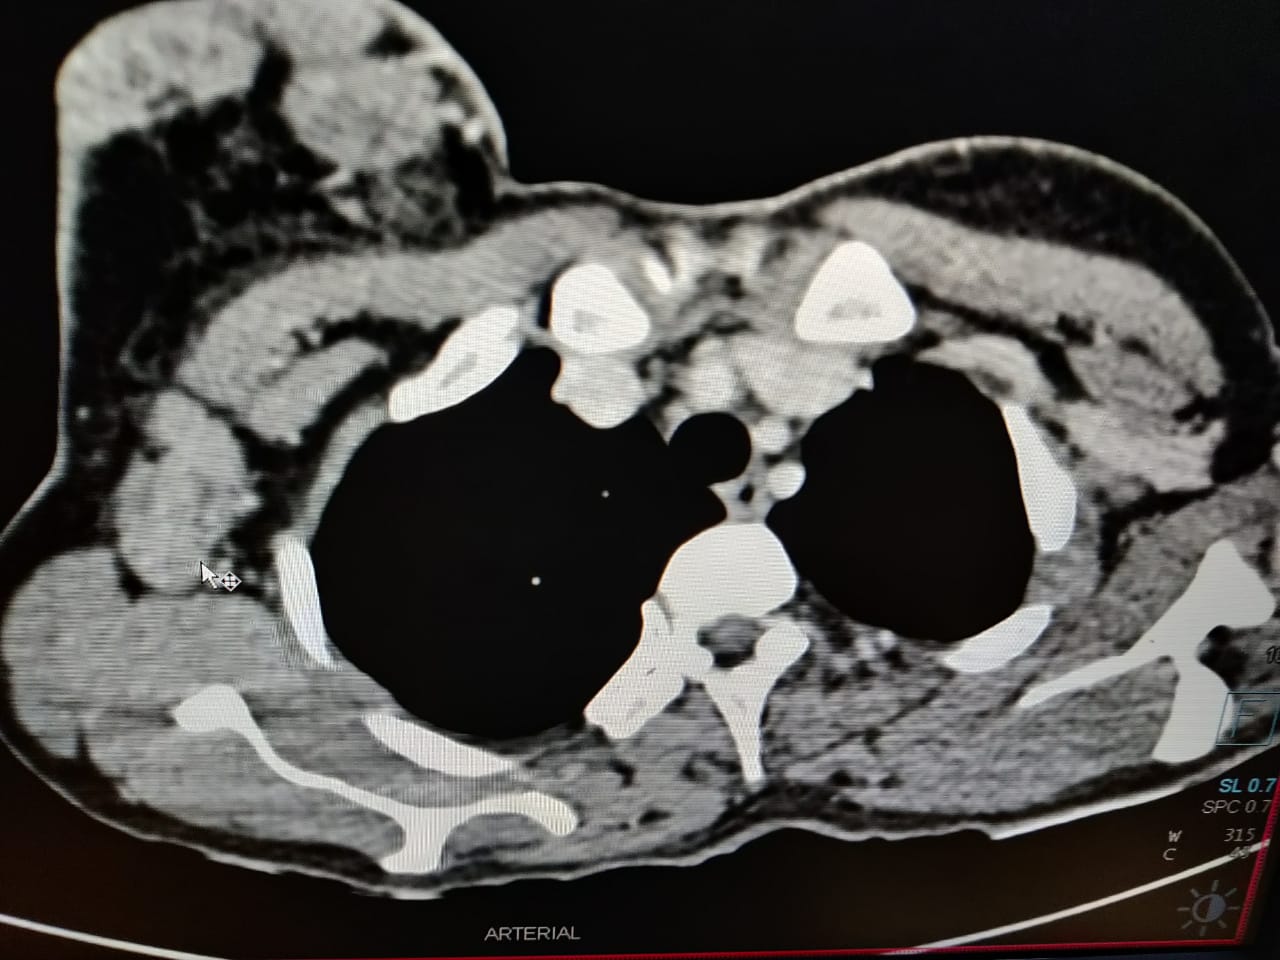

CECT revealed breast lesion extending posteriorly to involve pectoralis major muscle and metastatic lesion involving lungs, liver and lumbosacral vertebrae, making it a stage 4 breast carcinoma. []